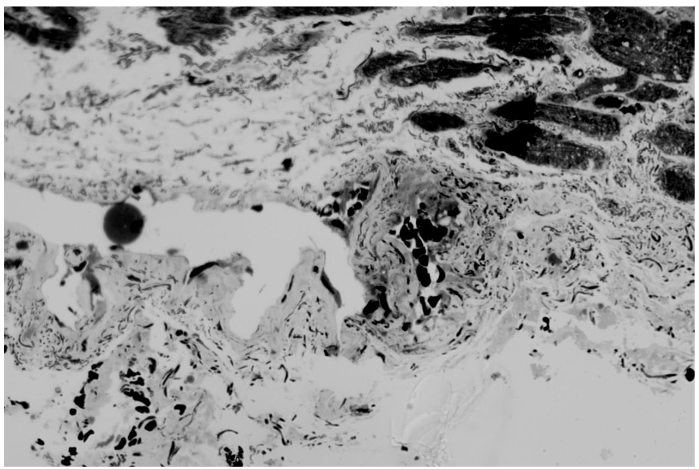

Cardiomyocytes are not wide in transverse diameter. Interstitial edema is expressed. Microcirculatory bed vessels vary in profile lumen width and wall thickness. The vessel wall is unevenly thickened, especially in large arterioles. Opposite walls merge and form bridges that unevenly block the profile lumen in several areas. Closure of opposite walls in a large arteriole leads to the formation of a new profile lumen in the vessel wall. And also closure of opposite walls of a large arteriole leads to the formation of a convolute consisting of forming chambers with the presence of erythrocytes in the lumen of the chambers. Such a convolute fences off part of the arteriole from the general lumen. On the pathological growth scale 3 points.

The closure of opposite walls in a large arteriole leads to the formation of a new lumen of the profile in the vessel wall. And also the closure of opposite walls of a large arteriole leads to the formation of a convolute consisting of forming chambers with the presence of erythrocytes in the lumen of the chambers. Such a convolute fences off part of the arteriole from the general lumen. On the scale of pathological growth 3 scopes.

Cardiomyocytes are different in width with prevalence of thicker ones. Walls of small arterioles are slightly thickened. Large arterioles with pronounced thickening of the walls and their numerous invaginations into the lumen of the vessel profile are presented. Takes place formation of bridges in such vessels. It is interesting to observe a very large arteriole of unusual configuration, having two separate large lumen profiles and invaginations of the walls into these lumens. And also taking place closure of opposite walls of the arteriole and the presence of an isolated lumen in the wall of the arteriole. This patient has a small arteriole that has formed a convolute of several chambers. And also, there are small arterioles De Novo located close to each other. On the scale of pathological growth from 3 to 4 points.

Cardiomyocytes vary in diameter, many are wider. Proliferation of connective tissue between cardiomyocytes. Interstitial edema. Arterioles vary in profile size from large to medium and small. Large arterioles with unevenly thickened walls as well proliferation of cellular elements of the vessel wall are observed. Large arterioles have a pronounced process of invagination of opposite walls into the profile lumen. Bridges are formed in the profile lumen of large arterioles, sometimes in large quantities. Small arterioles are also characterized by the presence of a bridge and the formation of two profile lumens. Several profile lumens are formed in a large arteriole in the vessel wall, which indicates the presence of a convolute. According to the pathological growth scale, 3 points.

Ischemic heart disease is a rather insidious disease. A significant role here is played by atherosclerotic damage to both the coronary main vessels and the primary link of the microcirculatory system, the arterioles. The main resistance vessels of coronary arteries are arterioles (with a diameter of <200 mk) and play a key role in the physiological regulation of myocardial reperfusion. The regulatory mechanisms of arterioles can be further divided into large arterioles (100-200 mk that mediate dilation), medium arterioles (40-100 mk), and small arterioles (less than 40 mk). The studies we conducted on atherosclerosis of arterioles in men of different ages visualized more or less the same changes, while the assessment scores varied from 3 points in one patient to between 3 and 4 in 3 patients. The visualization of the biopsy from patient 1 indicates that this is a relatively young heart. The patient is 46 years old. There is no hypertension in the cardiomyocytes and no proliferation of myofibrils. Ischemic heart disease reveals atherosclerotic arterioles. There is pathological growth of the intussusception type. Characteristic invagination into the lumen of the arterioles and the formation of bridges take place. Unlike the first patient, who had a slight wall thickness, the three others showed changes in wall thickness of varying degrees of severity. This is also a negative factor in atherosclerosis of arterioles.

The increase in diameter and thickening of the walls of arterioles during atherosclerosis occurs due to the proliferation of cellular elements, where smooth muscle cells play a very important role. While under physiological conditions, during reperfusion, arterioles can change the sizes of their luminal diameters, in ischemic disease, the growth factor plays a significant role. The increase in the diameter of arterioles occurs up to a certain limit, after which further changes occur in the manner of intussusception. The number of arterioles involved in this process is significant, whether they are large with a diseased diameter or small. This determines what arterioles can subsequently form De Novo. At the same time, the formation of bridges is also a negative process, as it can obstruct normal blood flow. Four patients are characterized by the presence of formed or forming convolutis. This is also a negative point, as it leads to a violation of blood flow. The term convolutes means multi-chambered, similar to the capillaries of the brain in hypertension. We can assess the visualization of atherosclerotic arterioles on a 5-point scale of pathological growth in the manner of intussusception. The term of intussusception angiogenesis, arteriogenesis is indicate the ways of new capillaries arteries and venous formation from previous.